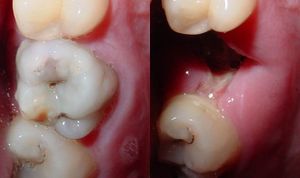

| Destruction of a tooth by cervical decay from dental caries | |

هو تخرب يصيب نسج السن الصلبة بدءاً من طبقة الميناء enamel ثم يصل إلى طبقة العاج محدثاً حفرة قد تزداد اتساعاً وعمقاً لتصل إلى اللب الذي يحتوي الأوعية الدموية والأعصاب.

حدوث التسوس وتطوره

تقوم الحموض الناتجة من عملية تخمر السكاكر بحل العناصر المعدنية والعضوية التي تدخل في تركيب ميناء السن فتبدو المنطقة بيضاء طبشورية وذات ملمس خشن. ولدى تزايد إنتاج الحموض وعدم تطبيق الفلوريد الموضعي على الأسنان الذي يقوم عادة بإيقاف تطور التسوس، يتهدم الميناء وتصل الإصابة إلى العاج مشكلة حفرة التسوس التي يمكن ملاحظتها سريرياً ويبدأ الإحساس بالألم لدى التعرض إلى مؤثرات خارجية من سخونة وبرودة أو الضغط أثناء المضغ. عند إهمال معالجة التسوس في هذه المرحلة يزداد التخرب وتصل الإصابة إلى لب السن الذي يصاب بالالتهاب وترافقه موجات حادة من الألم وخاصة في أثناء الليل. إن عدم تطبيق المعالجة الملائمة في هذه المرحلة يؤدي إلى تموت اللب وإصابته بالتعفن وتتكون الخراجات الحادة والمزمنة والآفات الذروية التي تنتهي بقلع السن المصابة.

يقوم طبيب الأسنان بإزالة جميع أنسجة السن المتلينة والمصابة بالتسوس بوساطة الأدوات اليدوية وأجهزة حفر الأسنان الدوارة ثم تنظف حفرة التسوس جيداً وبعد ذلك ترمم بمواد حاشية معدنية كالملغم amalgam الذي يتألف من مزيج من الزئبق والفضة والقصدير والنحاس، أو بمواد مرممة بلون الأسنان من نوع الراتنج أو الإسمنت الزجاجي الذي يتميز بالالتصاق الجيد وإطلاق الفلوريد. لدى وصول آفة التسوس إلى لب السن يقوم طبيب الأسنان باستئصاله وحشوه بالمواد الملائمة وإتمام ترميم السن.